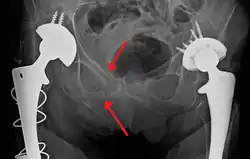

Fractures of the superior (in two places) and inferior pubic rami on the person's right, in a person who has had prior hip replacements

Classification